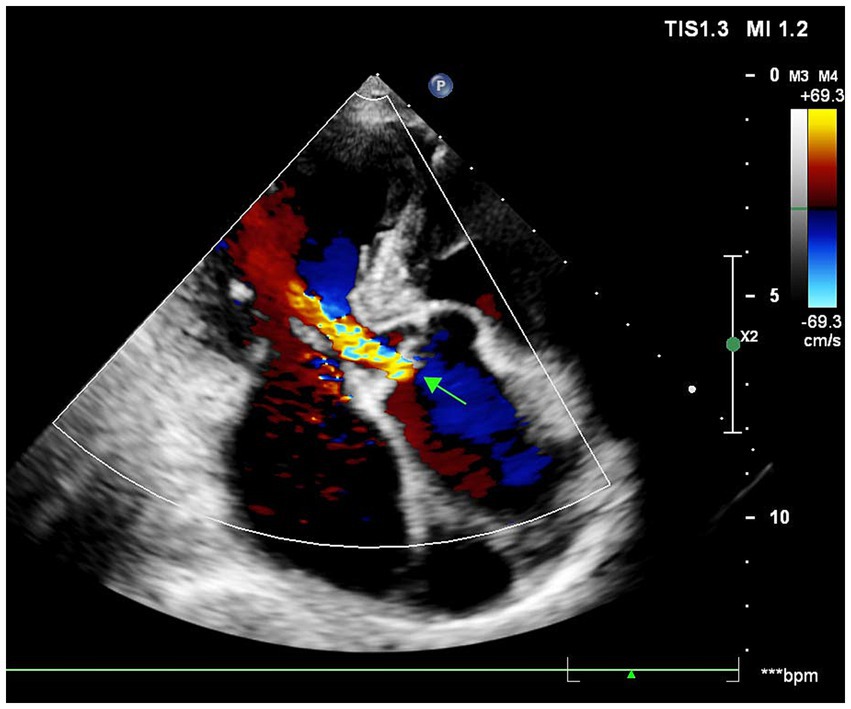

Figure 2

Echocardiographic features of aortic valvulopathy.

A 70-year-old male presented with recurrent substernal chest tightness, described as pressure-like, persisting for 1 week prior to admission. His past medical history included hospitalization for unexplained chest tightness 5 years ago. He also disclosed multiple unprotected sexual partners in his youth. He was a lifetime non-smoker, had no history of hypertension or diabetes mellitus, and his body mass index was 23.5 kg/m2. Electrocardiogram showed normal findings. The patient denied any family history of hypertension or cardiovascular disorders. Upon admission, vital signs were within normal limits, demonstrating a regular heart rate of 78 bpm and normotensive blood pressure (110/70 mmHg). Physical examination revealed diminished breath sounds bilaterally, with cardiomegaly noted in the left lower chest. Cardiac auscultation demonstrated a diminished, forceful apex beat and a grade 3/6 systolic blowing murmur at the apical region. The abdomen was soft and non-tender, without hepatosplenomegaly, rebound tenderness, or guarding; Murphy’s sign was negative. No lower extremity edema was present. High-sensitivity C-reactive protein (hs-CRP) was 2.4 mg/L. Mild dyslipidemia was noted with a low-density lipoprotein cholesterol (LDL-C) level of 1.76 mmol/L and a high density lipoprotein cholesterol (HDL-C) level of 0.81 mmol/L. Cardiac troponin I was 2.26 ng/dL and creatinine kinase myocardial band was 27.6 U/L. Serological testing revealed a non-reactive RPR (titer 1:1) but a positive Treponema pallidum particle agglutination (TPPA), confirming discordant serology. The initial electrocardiogram was unremarkable. However, a subsequent ECG revealed left ventricular hypertrophy (LVH) with ST-T changes in collateral leads and pathological Q waves in leads V1–V3 (Figure 1). The chest radiograph demonstrated mediastinal widening consistent with aortic dilation. A non-contrast cardiac computed tomography (CT) scan was performed to assess the aorta and coronary calcification, which revealed a thoracic aortic aneurysm (diameter 5.2 cm) but, remarkably, a coronary artery calcium score (CACS) of 0, indicating the absence of any calcified atherosclerotic plaque. Echocardiography revealed significant cardiac abnormalities including left atrial and ventricular enlargement with phasic left ventricular wall motion abnormalities, mild aortic valve thickening accompanied by moderate diastolic regurgitation, and severe mitral regurgitation. The study also demonstrated grade III left ventricular diastolic dysfunction and markedly reduced systolic function with an ejection fraction of 29%. Collectively, these findings suggested secondary mild pulmonary hypertension in the setting of significant left heart disease (Figure 2).